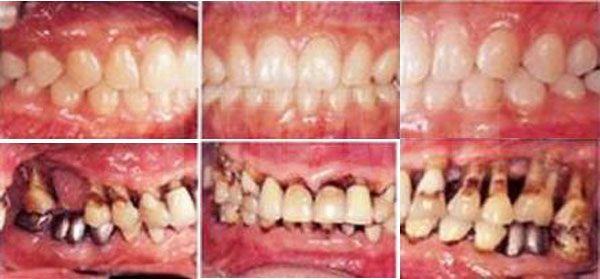

-Олон жил тамхи татсаны эцэст та шарласан шүдтэй болох, шүд унах нь 1-1.5 дахин их, шүд сулрах ба буйлны үрэвсэл